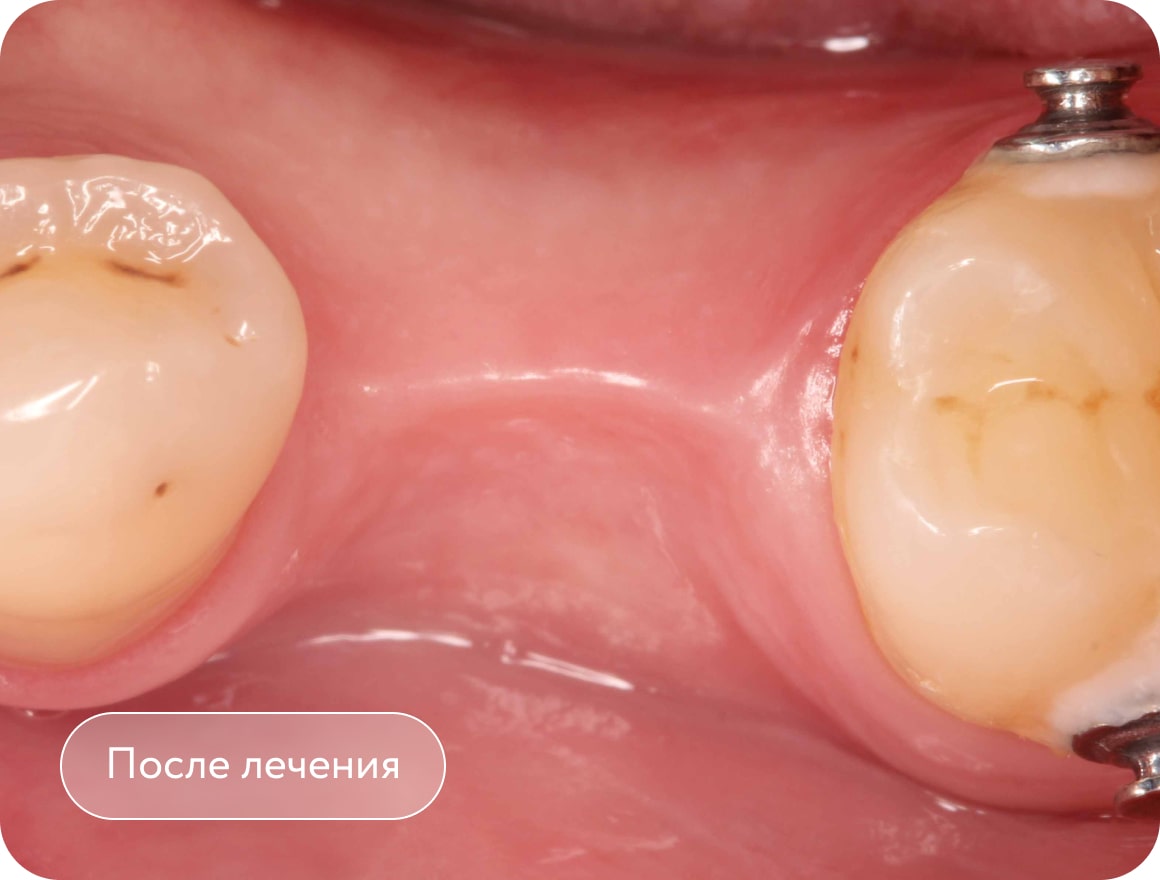

Установка мини-винта, вытягивание 2 моляра с помощью резинок. Создание места для имплантации в области 1 моляра. Срок лечения 3 месяца